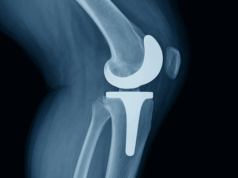

Is Age Still a Barrier to Cementless Fixation? Some Say No.

A single-institution series of 142 cementless TKAs in patients older than 75 years reported excellent mid-term survivorship, with 99.3 percent aseptic and 98.6 percent...